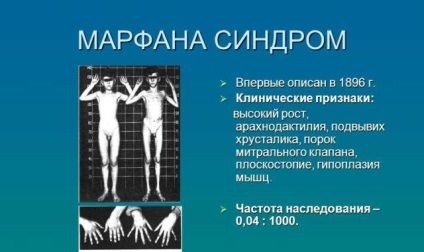

Neonatalnaya forma sindroma marfana klinicheskoe opisanie i kompleksnyj podhod k diagnostike i lecheniyu tema nauchnoj stati po klinicheskoj medicine chitajte besplatno tekst nauchno issledovatelskoj raboty v elektronnoj biblioteke kiberleninka (Тип файлу jpg)

Neonatalnaya Forma Sindroma Marfana Klinicheskoe Opisanie I Kompleksnyj Podhod K Diagnostike I Lecheniyu Tema Nauchnoj Stati Po Klinicheskoj Medicine Chitajte Besplatno Tekst Nauchno Issledovatelskoj Raboty V Elektronnoj Biblioteke Kiberleninka